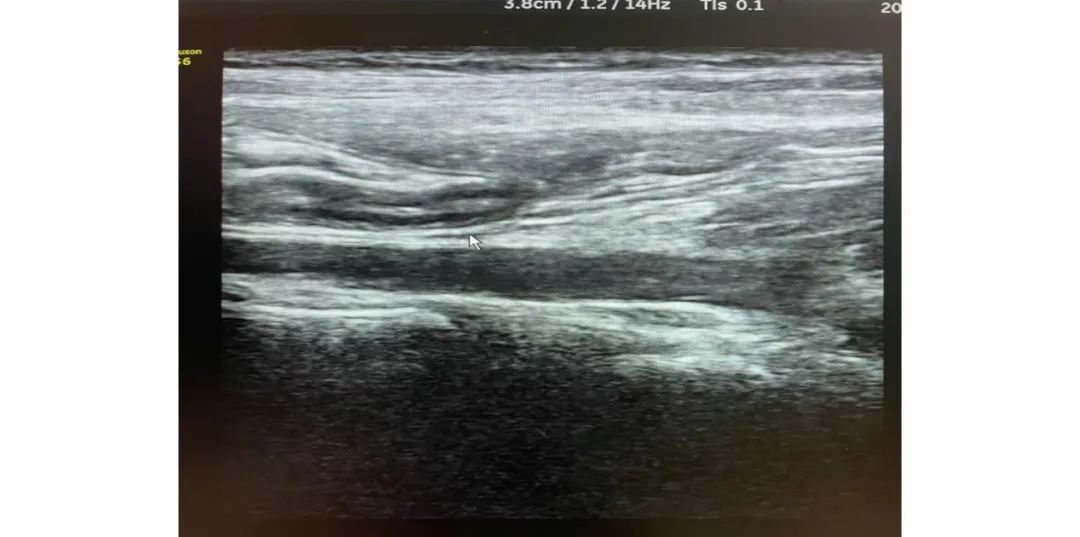

正常闌尾的超聲圖像特征

1.細(xì)小管狀結(jié)構(gòu);2.盲端;3.可壓縮性;4.無多普勒信號(hào);5.周圍無炎性脂肪包繞。